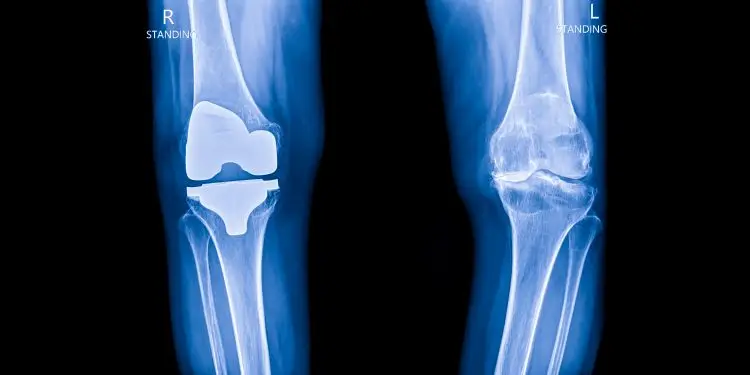

That is how long my astoundingly patient orthopedic surgeon has cautiously suggested that I might enjoy a knee replacement… or two.

It was simply time for a new knee, a knee that would enable me to walk without restriction, to climb and descend stairs with an alternate gait, without discomfort or unease. Time to have the tool I needed to best enjoy my retirement of travel, gardening and physical exertion and long-term health.